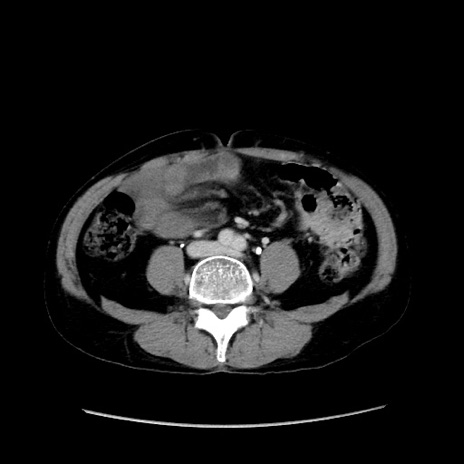

症例37(横断像)

【症例】40歳代 男性

【主訴】腹痛

【現病歴】4時間ほど前に電車に乗車中に臍部上より腹痛出現。徐々に増悪し起立困難となり、救急外来受診。生ものは数日食べていない。今朝お雑煮を食べた。

【身体所見】BT 36.8℃、BP 117/84mmHg、HR 91/min、SpO2 97%、苦悶様、腹部:臍上部広範囲圧痛あり、反跳痛±

【データ】WBC 8100、CRP 0.03